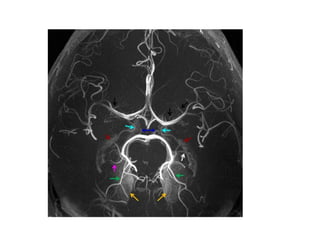

5- Yellow arrow demonstrate

stenosis of-

1- right ICA

2- right vertebral A.

3- right PCOM

4- Right MCA

6- MRA demonstrate

stenosis of -

1- vertebral artery

2- basilar artery

3- PICA

4- AICA

7- MRA demonstrate Right

MCA-

1- Aneurysm

2- AVM

3- Thrombus

4- Hypoplasia

9- Light blue arrow

demonstrate-

1- Anterior choroidal artery

2- Posterior choroidal artery

3-PCOM

4- PCA

10- white arrow denotes-